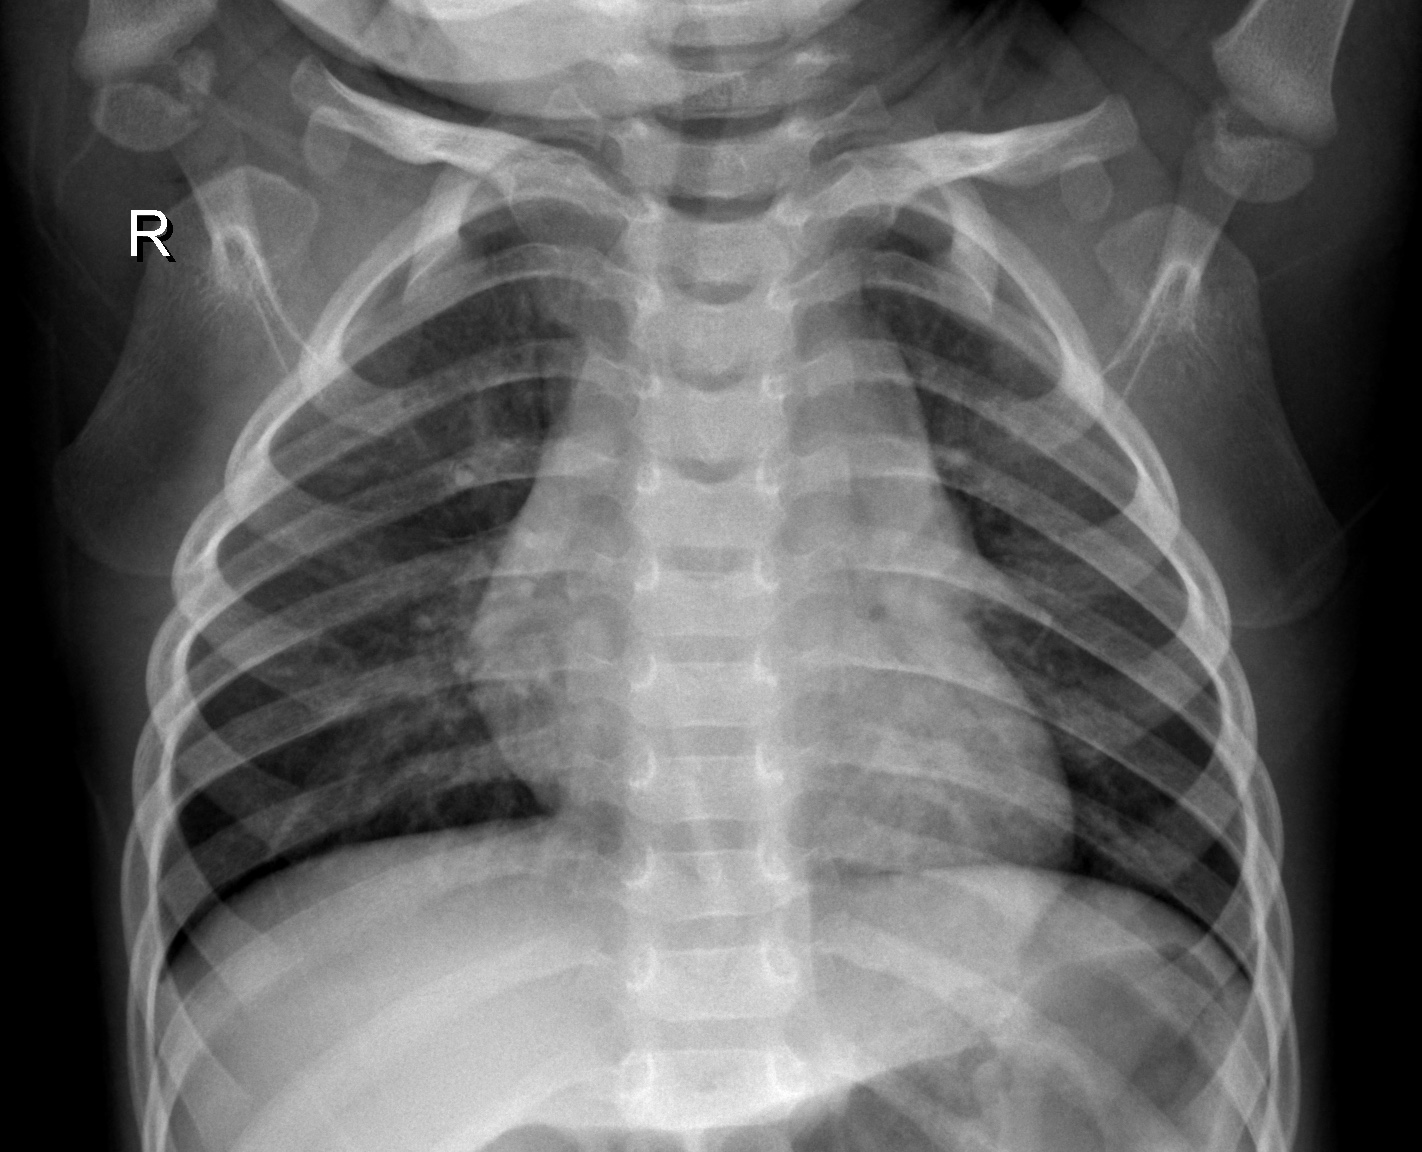

7. Application of RCRI Measure in Image Processing

To ensure the accuracy and reliability of our results, we have taken into account six chest X-ray images from the publicly available chest X-ray 2017 dataset, contributed by kermany2018labeled. These images include samples from healthy individuals and patients diagnosed with pneumonia. For analysis, each X-ray image was converted into a 50×5050\times 50 pixel grid, resulting in 2500 cells per image. The intensity of the gray level of each cell was recorded as a real number ranging from 0 (black) to 1 (white), effectively capturing the grayscale distribution of the image. The α\alpha and β\beta are take as 55.

Using these six images, we generated all 36 possible pairwise combinations. For each pair, we are estimating the Relative Cumulative Residual Information (RCRI), which serves as a measure of discrepancy between the Gray level distributions of the images.

As illustrated in Figure 2, images (a), (b), and (c) correspond to normal chest X-rays, while images (d), (e) and (f) represent pneumonia-infected cases. The calculated RCRI values are presented in Table 10. The matrix reveals distinct clustering patterns that effectively separate the two groups. The top-left 3×33\times 3 submatrix, which includes comparisons among normal images (a, b, c), shows RCRI values ranging from 0.0559 to 0.0637, indicating strong similarity within this group. Similarly, the bottom-right 3×33\times 3 submatrix, corresponding to comparisons among pneumonia-infected images (d, e, f), shows moderately higher but internally consistent RCRI values between 0.1854 and 0.2533, reflecting similarity within this second group. In contrast, RCRI values for comparisons between normal and pneumonia images fall into an intermediate range (approximately 0.0858 to 0.1204), distinctly separating the two classes. These patterns support the application of RCRI as an effective statistical measure for distinguishing grayscale intensity distributions, highlighting its potential in medical image classification and diagnostic support. This consistent difference underscores the effectiveness of the RCRI measure in distinguishing between normal and pneumonia-affected X-rays based on their pixel intensity distributions, supporting its application in medical image analysis for diagnostic purposes.

Refer to caption

(a)

(b)

(c)

(d)

(e)

(f)

Figure 2. Chest X-ray Images

Table 11. Matrix of Relative Cumulative Residual Information (RCRI) for Chest X-ray Image Pairs

a b c d e f

a 0.0512 0.0564 0.0559 0.0858 0.0983 0.0955

b 0.0564 0.0652 0.0637 0.1030 0.1204 0.1156

c 0.0559 0.0637 0.0625 0.0996 0.1159 0.1114

d 0.0858 0.1030 0.0996 0.1854 0.2150 0.1984

e 0.0983 0.1204 0.1159 0.2150 0.2533 0.2334

f 0.0955 0.1156 0.1114 0.1984 0.2334 0.2197